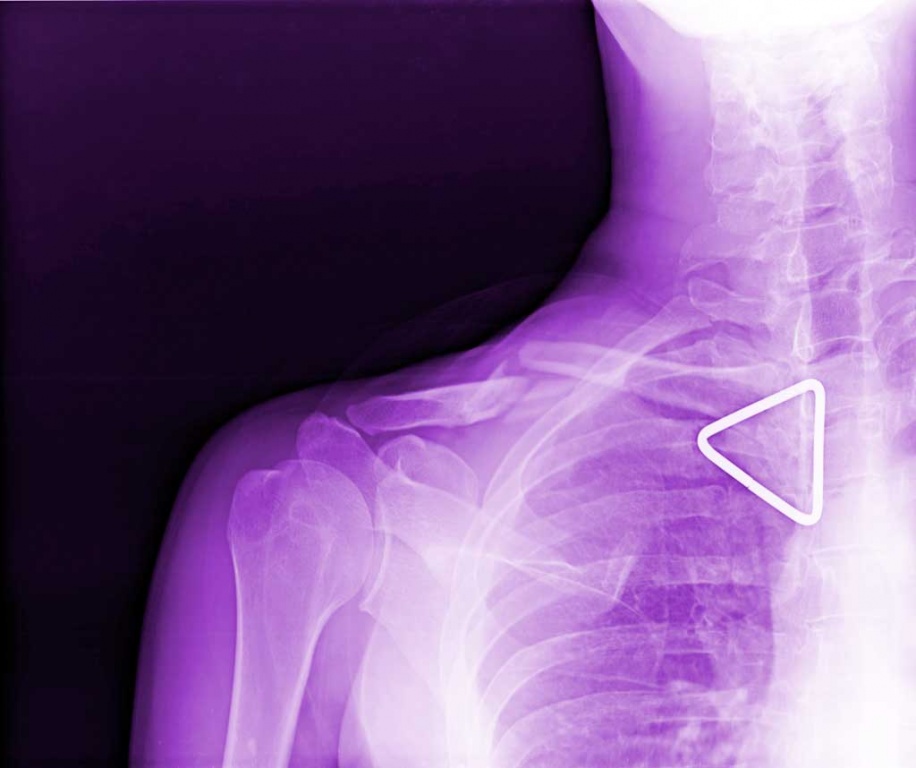

Per esempio è un dato di fatto che la clavicola rotta mi impedisca di scrivere agevolmente ma in realtà il problema è del mio cervello che mi fa scrivere solo cazzate, percui è inutile che mi lagno!